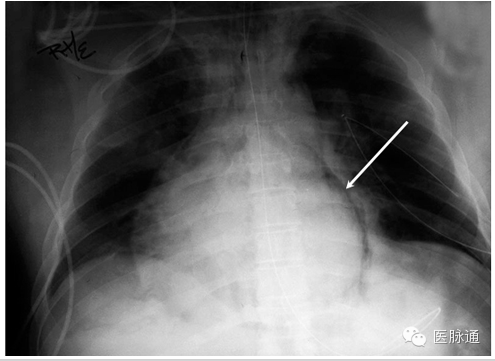

纵隔积气是指纵隔结构中存在游离气体。纵隔积气最常见于食道或相邻肺泡的创伤或医源性损伤。胸片中,游离气体可能形成解剖结构的轮廓。常见表现包括形成心脏影像的透X光细线轮廓(图4白色箭头),纵隔内纵向走形的气体,支气管壁双影征,或右侧肺动脉周围透光区域(即“动脉周围戒指征”)。在侧位胸片上胸骨后间隙最易检测到气体。纵隔积气的气体是固定的且不会移动到最高。

图4